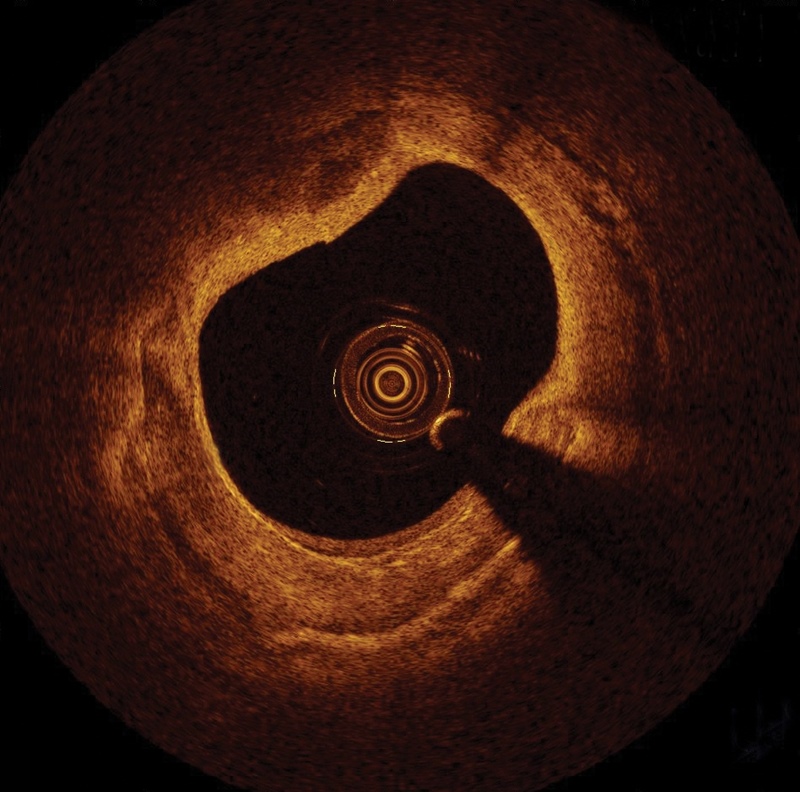

Inside blood vessels: the OCT view

OCT images allow physicians to view the inside of a blood vessel. Credit: St Jude Medical.